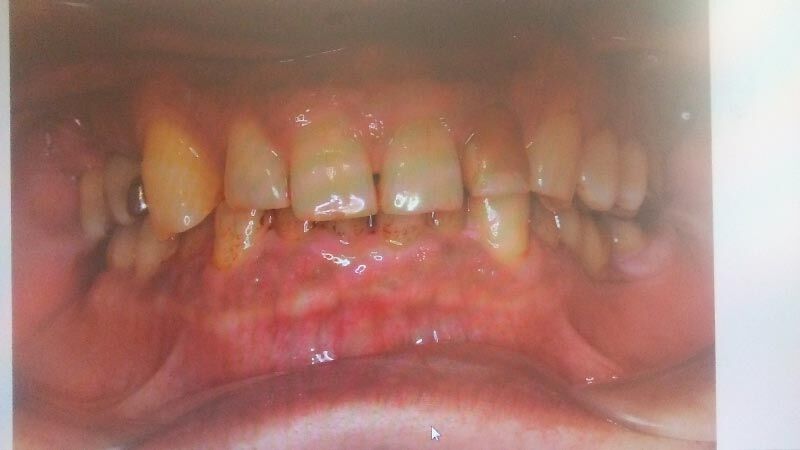

新しい病院へ行く。まずは、口の中の初期値の写真をとる。鏡のようなものをくわえて、裏側も取りました。いずれも、おぞましき写真です。歯の裏ヤニで真っ黒^^;^^;。

そして鬼のような歯石とりが始まる。上3回、下3回、計6回に分けてやる。部分麻酔をかけて、歯の根っこの方まで歯石をとります。一言でいうと、苦行そのものです^^;^^;。